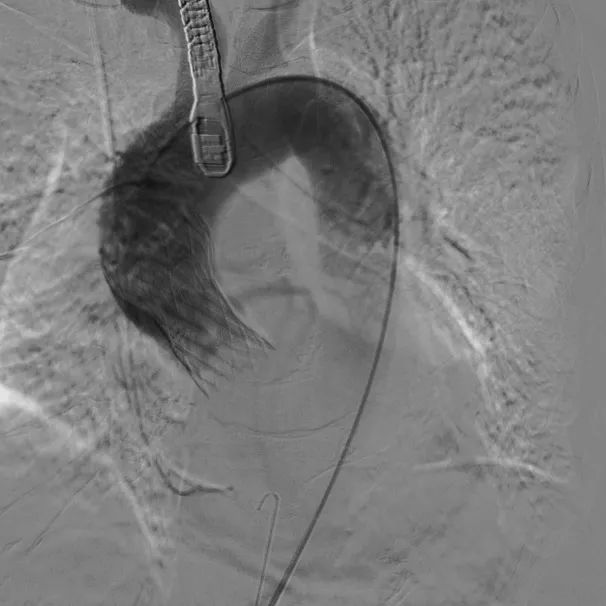

术中影像

根部造影;直头导丝顺利跨瓣

23mm球囊预扩,冠脉显影正常;输送器顺利过弓

初次释放,无冠窦畸形猪尾难以到达窦底,定位带来挑战;释放至工作位,瓣膜(AV29)位置偏低

瓣膜(AV29)完全回收后重新定位释放

瓣膜(AV29)工作位正交体位造影位置良好,左冠显影正常

瓣膜(AV29)完全脱钩释放后23mm球囊充分后扩,冠脉灌注良好

最后造影